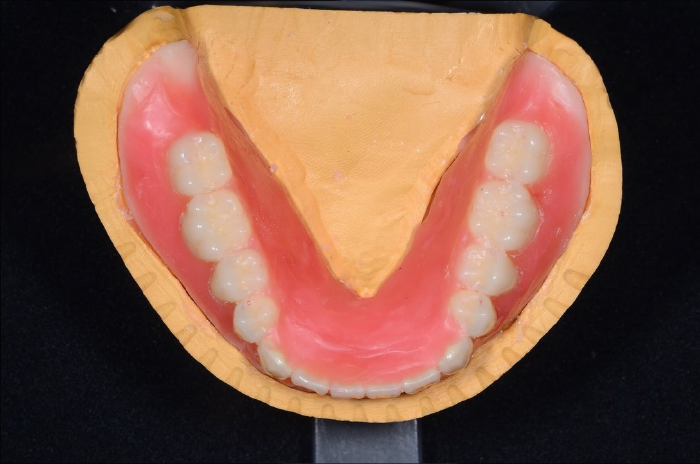

人工歯排列

入れ歯の歯を並べる過程の写真です。即時義歯ではパーツごとに模型の歯を削って、そこに人工歯を並べることを繰り返していきます。 歯を抜いた後の歯ぐきの形を想像しながらの作業は精密な診査と経験が必要になります。

治療用義歯

治療用義歯を使用しながら、下記内容を少しずつ整えていきました。

1. 噛み合わせの高さ

2. 顎の位置

3. 舌や口の周りの筋肉との調和